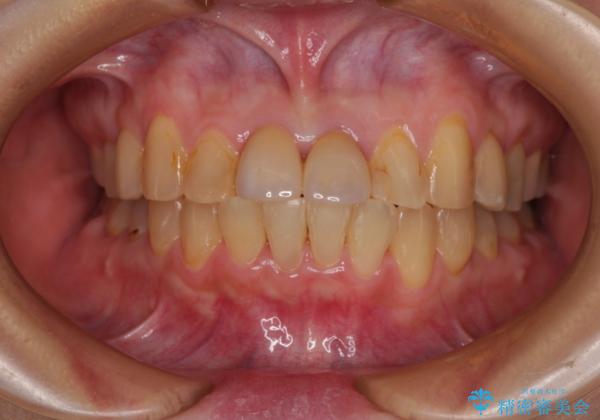

前歯のデコボコをワイヤー矯正できれいに整える

気になっていた前歯の変色も、矯正治療後にオールセラミッククラウンにて補綴治療を行うこととしました。

舌の突出癖により治療期間中に開咬となり、治療が長引きましたが、口元も治療前よりも引っ込めることができ、すっきりとした仕上がりとなりました。